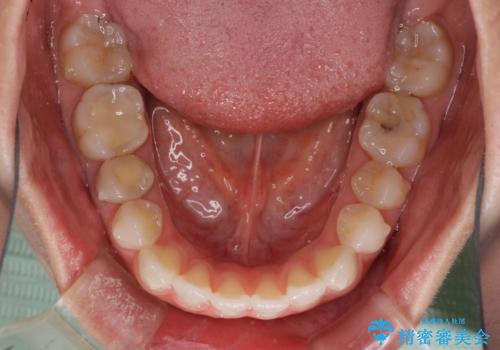

- 上下の前歯の反対咬合を気にして来院された患者様です。

インビザラインを用い、下顎はIPR(歯と歯の間を削る)と歯列全体を後方に移動させ、上顎は前歯を持ち上げることで、反対咬合を改善していくこととしました。

インビザラインによる反対咬合の改善は、上の歯が下の歯を乗り越えていく期間に咬み合わせが非常に不安定となり、治療が長期化することがあります。

こちらの患者様も、一時的に前歯でしか咬めない時期がありましたが、比較的早く咬み合わせが安定し、1年ほどで治療を終えることができました。